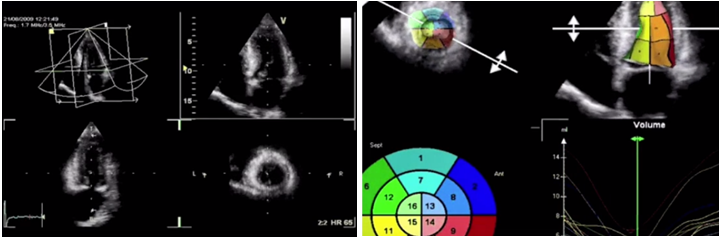

Методом выбора в оценке систолической функции миокарда является исследование фракций выброса левого желудочка при помощи эхокардиографии. Наилучшими являются измерения при помощи трехмерной эхокардиографии, а используемые иногда измерения в одномерном М-режиме по методу Тейхольца проводить нельзя, в связи с большим количеством неточностей и погрешностей. И при отсутствии трехмерной эхокардиографии исследование выполняется в двухмерном режиме по методу Симпсона.

Измерение ФВ ЛЖ в 2D режиме по Simpson

Измерение ФВ ЛЖ в 3D режиме

И разброс данных, получаемых при трехмерной эхокардиографии, даже у одного врача может составлять около 6%, а при двухмерной – около 10%.

Разница между измерениями в двухмерном и в трехмерном режимах может достигать 23%.

Стоит отметить, что положительной стороной исследования фракции с помощью эхокардиографии является ее доступность. Основные ее ограничения: от качества оборудования зависит качество изображения, имеет значение и опыт врача. Поэтому для серийной оценки фракции выброса левого желудочка необходимо использовать одно и то же оборудование, а измерения, желательно, чтобы выполнял один и тот же врач.